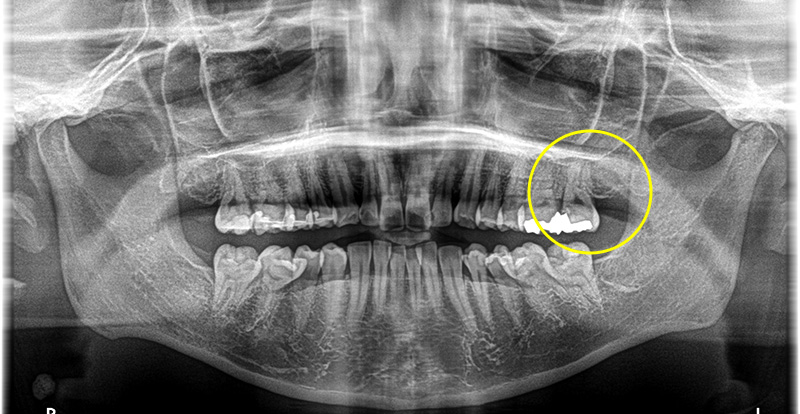

他院で骨が少ないと診断された方も、

まずはご相談ください

医院全体で1000本以上の実績

安心のインプラント治療

当院では1000本を超えるインプラント治療の実績に基づき、CTによる精密な診断のもと、安全性を優先した治療計画を立案します。 骨造成など難度の高い症例にも対応可能です。 失われた歯の機能と見た目を取り戻すための、良質な方法をご提案します。